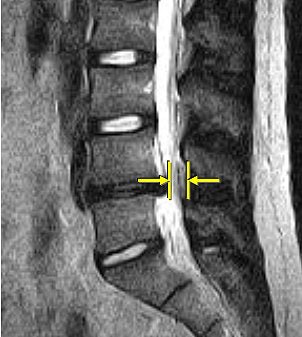

![]() |

| Above, nonaxial-loaded images. Below, axial-loaded images. Increase in stenosis at L4 level by 2.0 mm and left L4 spinal nerve root with axial loading. All images courtesy of Dr. Gerald Anzalone. |